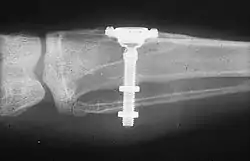

While studying bone cells in a rabbit tibia using a titanium chamber, Branemark was unable to remove it from bone. His realization that bone would adhere to titanium led to the concept of osseointegration and the development of modern dental implants. The original x-ray film of the chamber embedded in the rabbit tibia is shown (made available by Branemark).